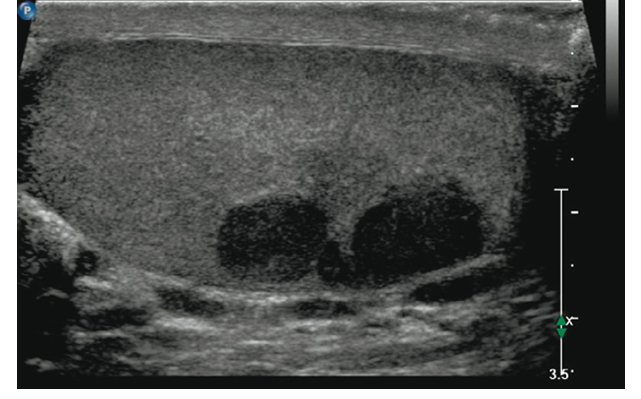

🔹 2. Інструментальні методи

УЗД яєчок з доплерографією — “золотий стандарт” первинної діагностики. Дозволяє відрізнити пухлину від кіст, запалення чи гідроцеле.